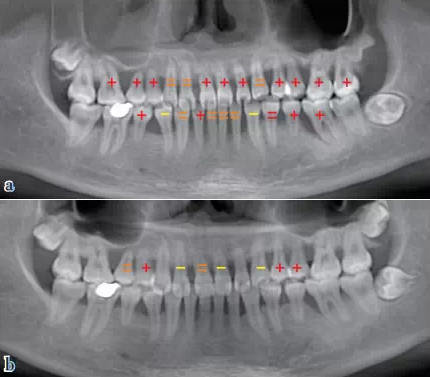

檢查 口外觀面部不對稱,張口時下頜左偏;牙齦紅腫出血,牙列欠整齊,牙間隙增大(圖1a),各項牙周臨床指標(biāo)見圖2a;CT體層片顯示牙槽骨廣泛吸收,嚴(yán)重者至根尖;右上頜竇炎癥(圖7a);CT圖像經(jīng)3D重建顯示牙尖交錯位異常。

QQ圖片20150710154752.png圖7 放射影像評估:與初診比較,牙槽骨骨量和骨密度明顯增加,上頜竇炎癥得到控制、明顯減輕;與初診比,牙齒松動顯著好轉(zhuǎn)(“+”表示松動Ⅲ度,“=”表示松動Ⅱ度,“-”表示松動I度),(a)初診,(b)兩年后評估

在該病例中,患者面部不對稱、張口偏斜均是咀嚼肌作用的表現(xiàn),反映了咬合系統(tǒng)的不協(xié)調(diào)。由此產(chǎn)生的咬合創(chuàng)傷促使牙齒松動、牙間隙增大、牙槽骨重度吸收,并進(jìn)而導(dǎo)致牙源性上頜竇炎。

在對該病例行SRP治療的基礎(chǔ)上,針對病因進(jìn)行了咬合干預(yù)治療。通過上述治療,該患者最終未行拔牙、牙髓聯(lián)合治療和手術(shù)治療,原病變較嚴(yán)重的患牙亦得以保存;其次,咬合不協(xié)調(diào)得到改善,牙松動度明顯減小,且因牙槽骨骨量明顯增加,牙源性感染被阻斷,上頜竇炎得以減輕;最后,由于神經(jīng)-肌肉作用趨于平衡,牙列較治療前排列更整齊,牙間隙減小。